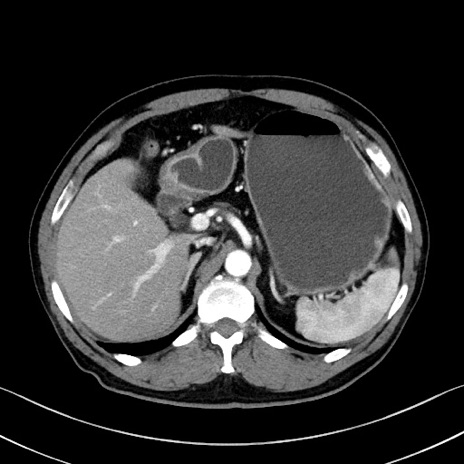

冠状断像

【症例】70歳代 男性

【主訴】腹部膨満、嘔吐

【現病歴】昨日より腹部膨満感出現。本日増悪し、仙痛出現。嘔吐あり、受診。

【既往歴】糖尿病、胆摘後

【身体所見】BP 149/80mmHg、HR 74/min、BT 35.9℃、腹部:膨満、軟、圧痛なし。腸雑音減弱あり。上腹部正中切開瘢痕あり。

【データ】WBC 13500、CRP 1.72